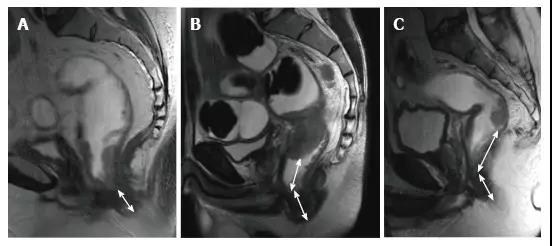

图 17. 新辅助放化疗后肿瘤重新分期。在不同患者的 T2 加权 MR 图像上分别显示(上:治疗前,下:治疗后)。A. 在 ypT0 直肠肿瘤中,治疗后的轴位图像显示正常的两层直肠壁(箭头),对应完全缓解;B. 在 ypT3 直肠肿瘤中,治疗后的轴位图像显示正常的双层直肠壁(箭头)。这是 MR 评估完全缓解的假阴性例子;C. 在 ypT0 直肠肿瘤中,原有肿瘤区域治疗后呈现厚的、纤维化的低信号强度疤痕(箭头)。

图 23. 放化疗对直肠肿瘤和周围切缘的影响。不同病人的 T2 加权轴位磁共振图像(上:基线,下:CRT 后)。A. 在没有 MRF 侵袭的 ypT2 直肠肿瘤中,在直肠系膜筋膜(箭头)处厚厚的低信号组织浸润导致过度分期;B. 在没有 MRF 侵袭的 ypT3 直肠肿瘤中,肿瘤的纤维性纤维性缩小,CRM 阳性可疑(箭头);C. 直肠肿块明显缩小,低信号强度浸润直肠系膜筋膜(箭头)。手术中证实肿瘤侵犯了直肠系膜筋膜。